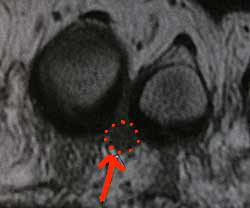

Les signes peuvent être moins typiques. Le diagnostic est basé sur l'examen. L'IRM peut apporter des renseignements dans les cas douteux (le névrome est entouré en rouge sur cette photo), mais l'imagerie n'est pas fiable à 100%